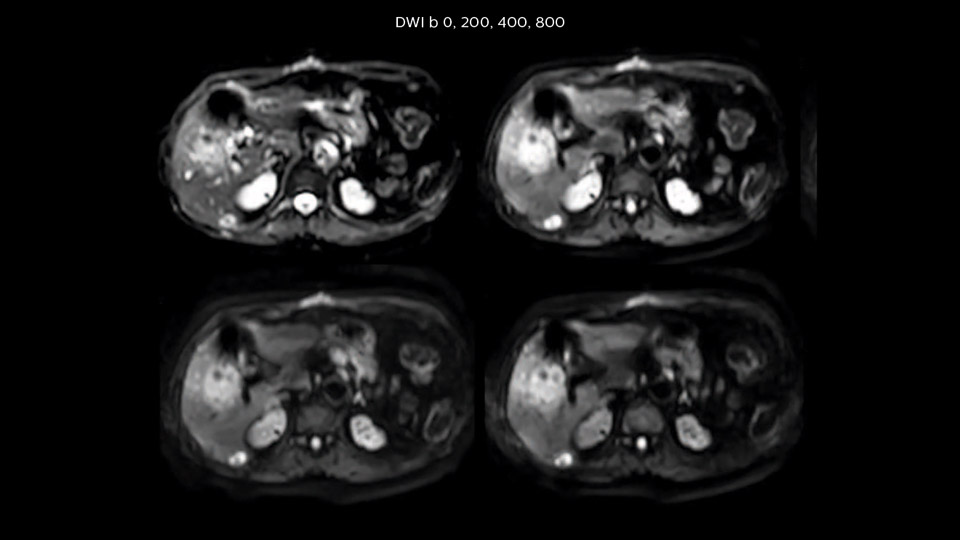

Dr. Baumann then implemented MultiVane XD for motion correction. It uses an extended reconstruction algorithm for imaging that is virtually motion free. “With MultiVane XD we get excellent motion-corrected images with high spatial resolution. We typically first optimize our scan for high image quality, and when satisfied with that, we try to reduce the scan time. So, we combined MultiVane XD with dS SENSE, which allows us to shorten the scan time,” he explains. “The performance of MultiVane XD in liver imaging is outstanding. MultiVane XD with dS SENSE is a powerful development in improving liver image quality.” “As we use breathhold imaging for T2-weighted liver scans, we depend on the patient’s ability to cooperate with the exam. This can present a real challenge when we are looking for small lesions, such as in our oncological patients. However, with MultiVane XD motion correction, we get excellent images. This is important for our surgeons, because they want to know exactly where the lesions are.”

In this example the image quality of the MultiVane XD images is evidently better than in the images without MultiVane XD. Ingenia 1.5T with dS Torso coil solution.

“Our liver exams are quite fast,” says Dr. Baumann. “If the patient tolerates it, we use an arms-up position to reduce the FOV and speed up the exam with dS SENSE.” “We acquire one transversal high resolution T2-weighted sequence with 3 mm slice thickness, for example for pancreas or liver lesions. Then we also add a T2 fat suppressed MultiVane XD SPIR sequence. We perform these two routinely in our liver imaging. We use high dS SENSE factors to significantly shorten scan times to 2-4 minutes, which can improve our protocol; it’s a very robust scan.” “We include mDIXON for the dynamic sequences because of the robust and homogeneous fat suppression we get with that. We had been using eTHRIVE, but we are now quite happy with mDIXON. Sometimes we use a medication to calm the bowels, to further improve the image quality.”